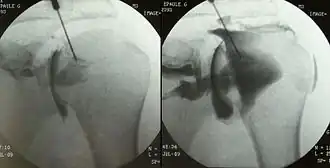

Shoulder arthrography can be used to study tears of the rotator cuff, glenoid labrum and biceps.[2] The type of contrast injected into the joint depends on the subsequent imaging that is planned. For pneumoarthrography, gas is used, for CT or radiographs, a water-soluble radiopaque contrast, and for MRI, gadolinium. Double-contrast arthrography can be used for more anatomically complex cases, though its use is relatively infrequent. The needle is radiographically guided into the glenohumeral joint space, after which the patient is evaluated by fluoroscopy, CT or MRI. The gadolinium in the contrast fluid yields a bright signal on T1 weighted images allowing for better evaluation of the joint capsule, the articular surface of the bones and, in particular, the labral cartilage. MR arthrography is most often used in evaluation of the hip and acetabular labrum, of the shoulder rotator cuff and glenoid labrum, and less often in the wrist.[2] Arthrograms can be diagnostic and therapeutic. Therapeutic arthrograms often distend the joint with cortisone and lidocaine, with a common site being the shoulder. Diagnostic arthrograms can be direct, as described above with penetration of the joint, or indirect, by a venous injection of contrast material and delayed imaging with CT or MRI.[2]